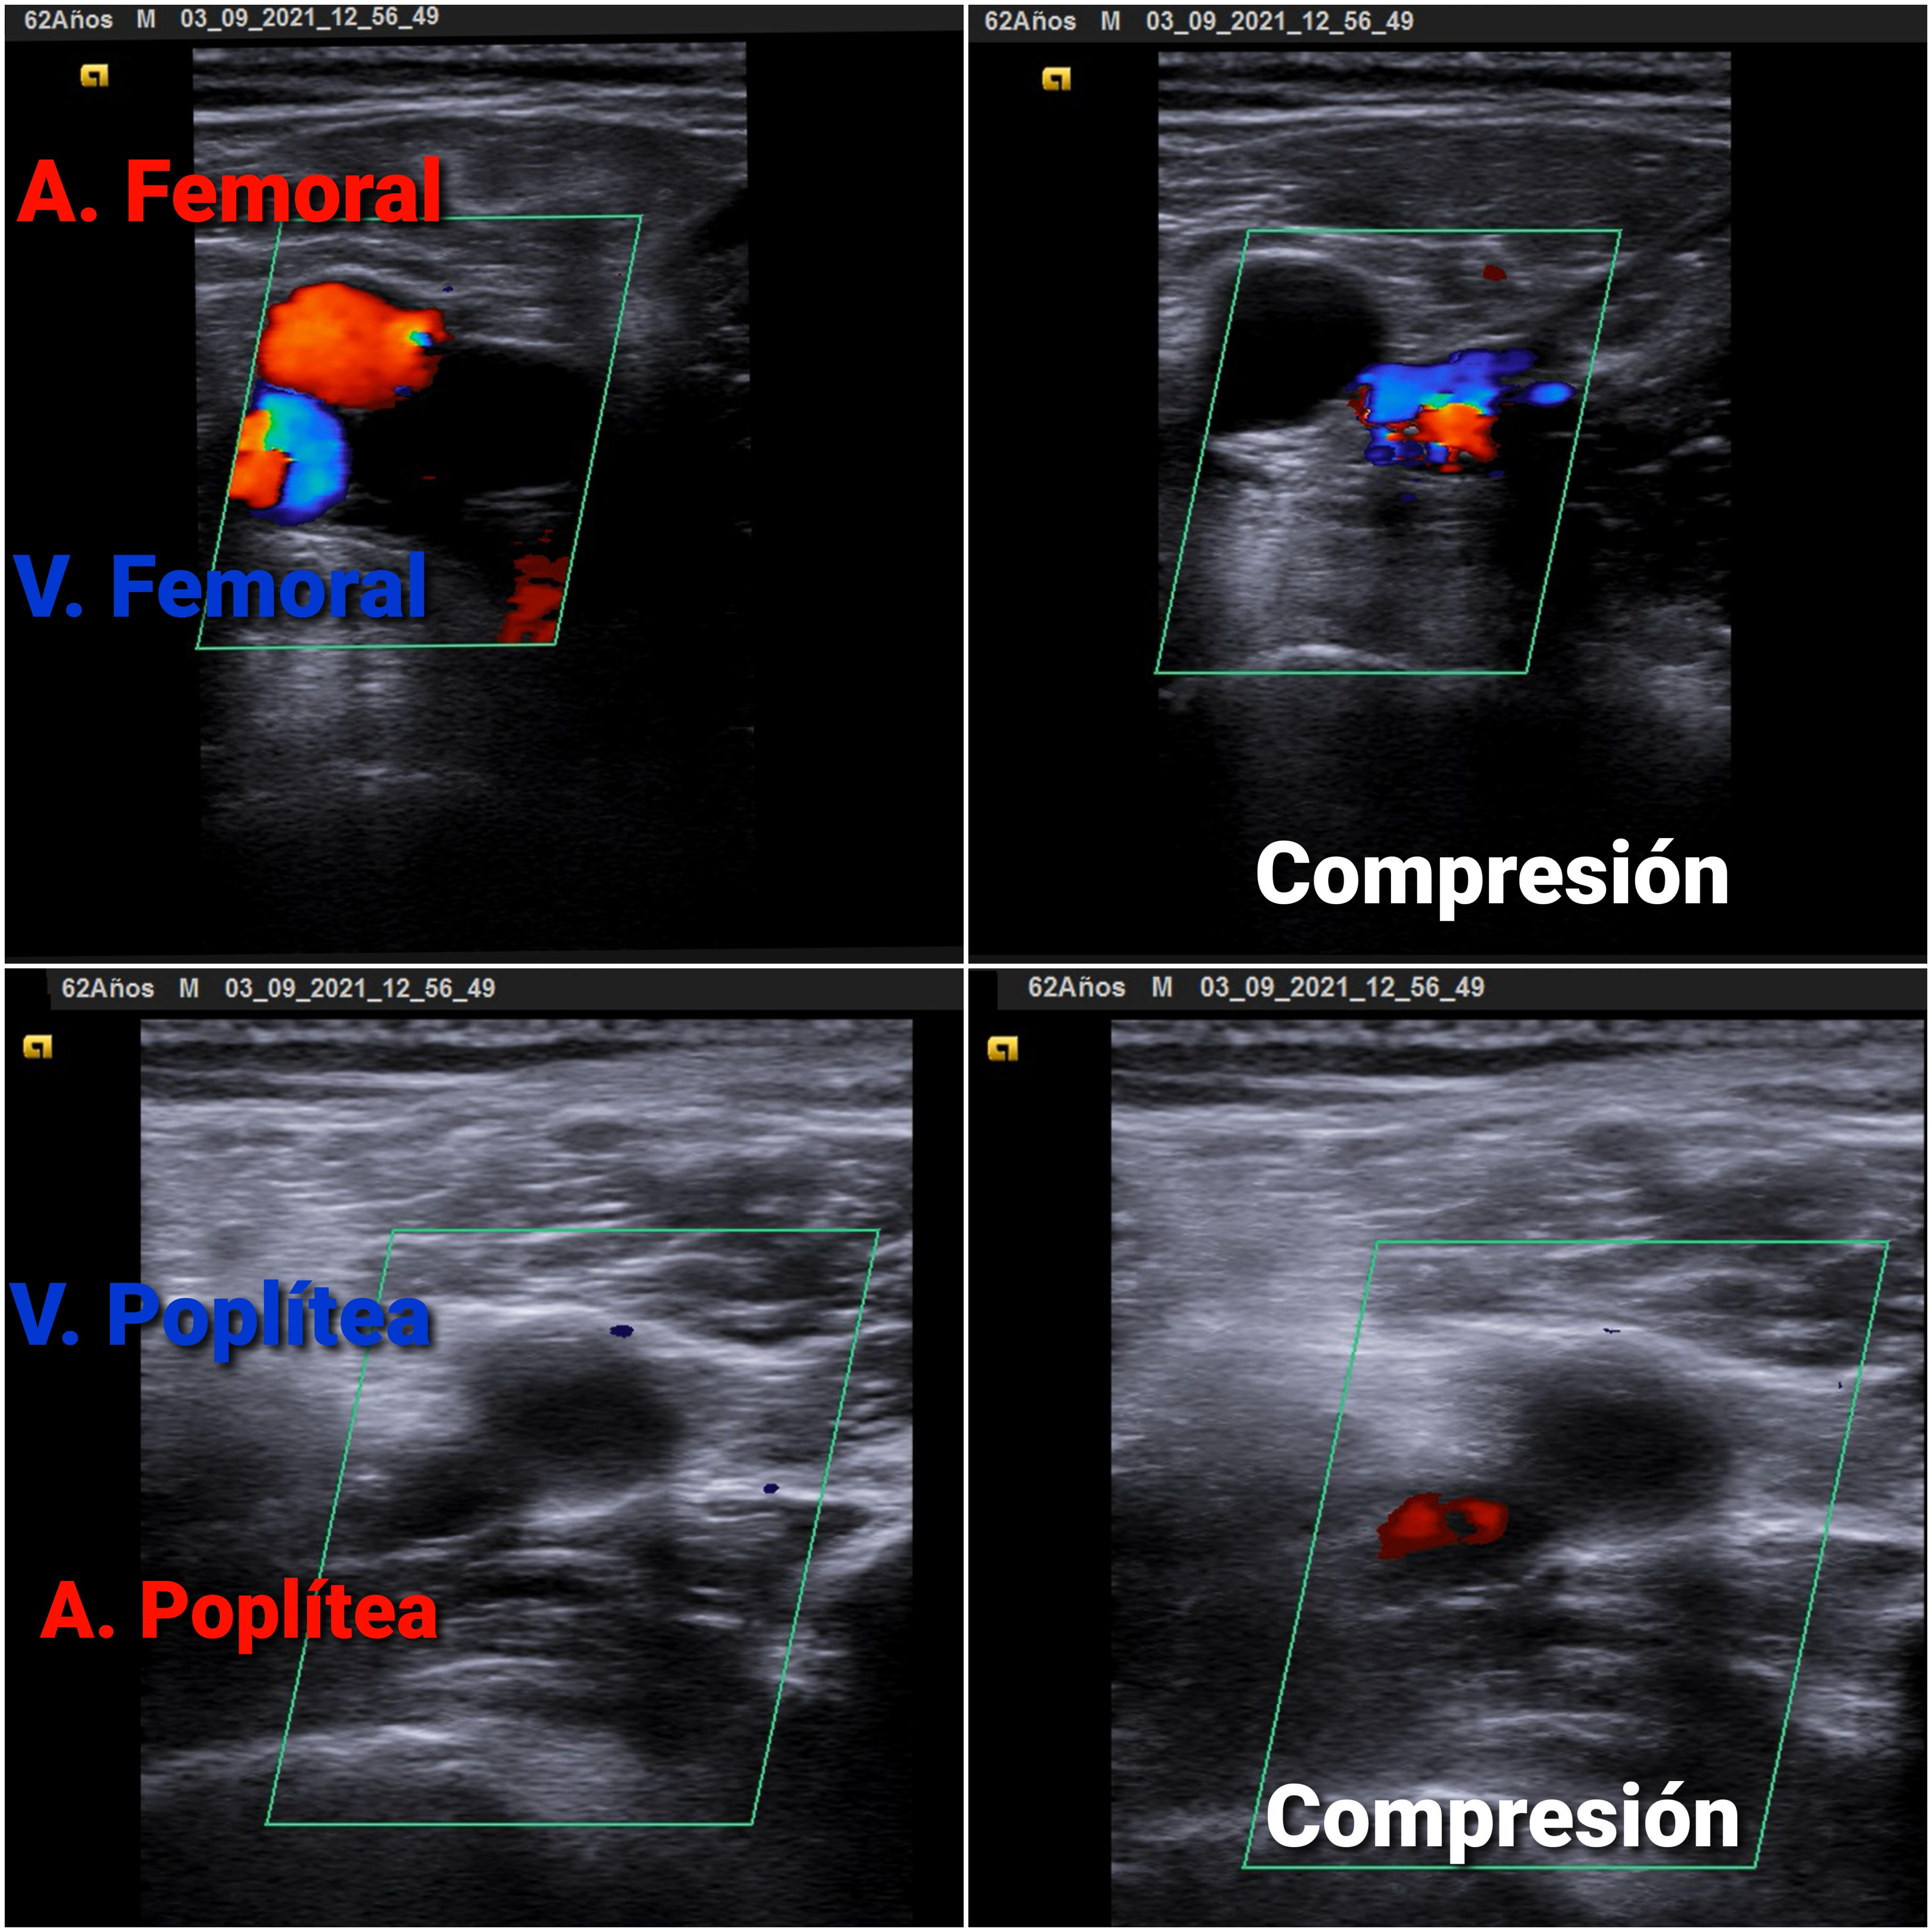

Eco Venosa: no colapso de vena poplítea derecha con signo de la oleada (-).

Trombosis Venosa Profunda (TVP) Poplítea con sospecha de Embolismo Pulmonar (EP)

El edema unilateral de una extremidad debe estudiarse siempre. Si fuera bilateral nos plantearemos la insuficiencia venosa crónica, con clínica compatible; si fueran por insuficiencia cardíaca, se acompañarían de disnea, ortopnea, crepitante y otros hallazgos. Si existe aumento de temperatura, calor y dolor nos plantearemos la celulitis.